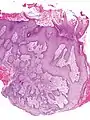

- Pseudoepitheliomatous hyperplasia (PEH) is a benign condition characterized by hyperplasia of the epidermis and epithelium of skin appendages,[33] with irregular squamous strands extending down into the dermis,[34] and closely simulating squamous cell carcinoma (SCC).[33]

Pseudoepitheliomatous hyperplasia (PEH), low magnification, with acanthotic squamous epithelium with irregular thick finger-like downgrowths into the underlying dermis.

PEH, high magnification, with reactive-appearing squamous downgrowths with no significant cytologic atypia.